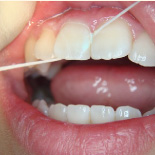

下の写真の一番左は実は治療前の写真です。痛みもなく一見問題なく入っている銀歯も除去してみると中に虫歯が。殺菌作用のある薬を詰めて治療中です。外からは分かりずらい虫歯も多いので定期検診がおすすめです。

- 治療前

- 除去

- 治療中